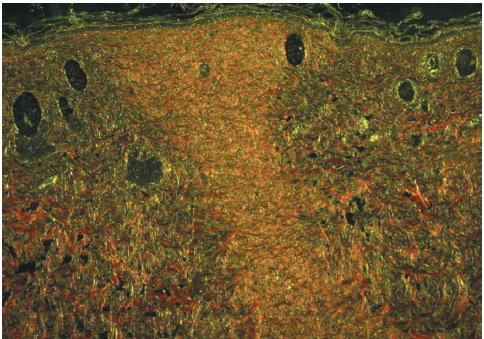

Após a preparação dos tecidos em lâminas para estudo microscópico, elas foram corados com hematoxilina/eosina e coloração de Picrosirius, as quais demonstram fibras de colágeno recém sintetizadas.

As lâminas para estudo do colágeno foram visualizadas em microscópio Zeiss, aumento de 100x, com luz polarizada, sendo obtidas três fotografias da área de fibrose de cada lâmina pelo programa Axion Vision. As microfotografias foram analisadas no programa Image J com o plugin Threshold Colour. Obtiveram-se o percentual de colágeno por análise de partículas de acordo com seleção e medidas de áreas com base na cor. Foram utilizadas a matriz 0-40 para cor vermelha (colágeno tipo I) e 45-120 para cor verde (colágeno tipo III), saturação 0-255 e brilho 5-225, segundo o protocolo padronizado por Bedoya et al. (2016).12

As figuras 1 e 2, obtidas atráves do estudo histopatológico, demonstram a proliferação de fibras colágenas nos grupos GC-30 e GCM-30, respectivamente. As fibras coradas em verde representam o colágeno tipo III e fibras coradas em vermelho representam o colágeno tipo I. Assim, é possível visualizar maior quantidade de fibras colágenas do tipo I (vermelho) no grupo GCM-30 (Figura 2), corroborando os resultados encontrados acima.

As figuras 3 e 4 representam a proliferação de fibras colágenas nos grupos GC-14 e GCM-14, respectivamente, sendo fibras em verde o colágeno tipo III e fibras vermelhas o colágeno tipo I.